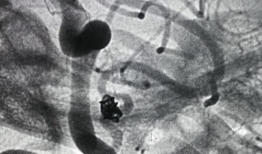

造影视频全过程,揭示血管奥秘与诊疗过程

你知道吗?最近我在网上看到一个超级有趣的造影视频全过程,简直就像是一部迷你电影,让我忍不住想要和你分享一下。这个视频详细记录了整...